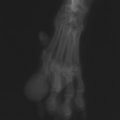

症例:右大腿骨遠位部の肉腫 クランバー・スパニエル 9歳 雌(未避妊)

2か月前から右後肢の完全挙上が認められ、消炎剤による内科治療で改善しないとのことで、他院から紹介来院した。

レントゲン検査

骨生検および病理組織検査

レントゲン検査所見から、骨もしくはその周囲組織に発生した腫瘍の可能性が考えられたため、病変部の細胞診検査およびジャムシディ生検針を用いた病変の骨生検を実施した。病理組織検査の結果、非上皮性の悪性腫瘍である“肉腫”と診断された。

内科治療に反応が乏しい四肢の跛行や疼痛は、本症例のように腫瘍が原因となっていることがあるため、レントゲン検査、骨生検等積極的に原因追及のための検査を実施することが必要である。骨の破壊を起こす悪性腫瘍は、非常に強い痛みを伴い、消炎鎮痛剤を用いても痛みを抑えることが困難となる。痛みの除去および腫瘍の治療のために断脚手術や抗がん剤等が必要となる場合があり、似た症状を示す整形外科疾患等とは治療法・予後が異なるため、その鑑別は重要である。